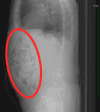

Figure 1

Figure 1. Contrast-enhanced CT scan of the abdomen and pelvis demonstrating multiple air-fluid levels within the colon, consistent with a diarrheal state (red oval).

CT: computed tomography